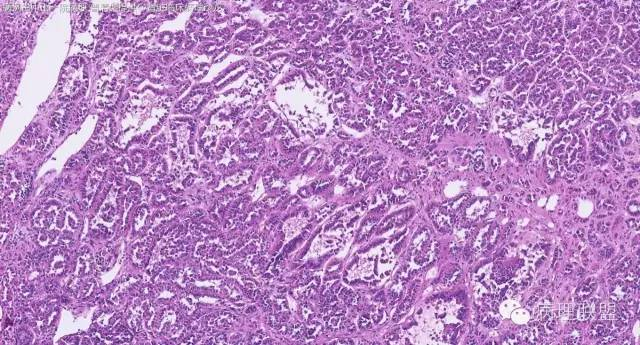

女性,50岁,肾上腺肿物(影像及手术均确认肿物位于肾上腺,界限清楚)。血压升高。(病例由 中山一院病理 曹清华提供,致谢!)

病例讨论

伴假腺样结构的肾上腺皮质腺瘤,合并髓脂肪瘤

从肿瘤的位置及镜下与肾上腺皮质的关系看,应该像是皮质来源肿瘤。假腺样结构的皮质腺瘤没有见过,似乎文献也还没查到。另外inhibina, melanA, syn均阴性(肿瘤旁正常皮质阳)感觉有点迷惑。。。请老师指教,有相关文献么?@武警嘉兴医院 周泉

假腺样是细胞粘附性差了导致。往往可以伴随黏液成分,组化上这几个抗体应该至少会有灶性阳性。

这个我再仔细看下。但,我们这例腺管结构不像是粘附差所致,是真的腺管;间质目前还没有看到有间质粘液变性区域;inhibina, syn, menlana是真的不阳,灶性都没有...